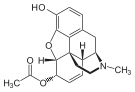

3,6-diesters of morphine

- Acetylpropionylmorphine

- 3,6-Dibutanoylmorphine

- Diacetyldihydromorphine (dihydroheroin, acetylmorphinol)

- Dibutyrylmorphine

- Dibenzoylmorphine (first designer drug)

- Diformylmorphine

- Dipropanoylmorphine

- Heroin (diacetylmorphine)

- Nicomorphine

Structures

| 3,6-diesters of morphine | ||||

|---|---|---|---|---|

Acetylpropionylmorphine Acetylpropionylmorphine |

3,6-Dibutanoylmorphine |  Diacetyldihydromorphine Diacetyldihydromorphine(dihydroheroin, acetylmorphinol) | ||

Dibutyrylmorphine Dibutyrylmorphine |

Dibenzoylmorphine Dibenzoylmorphine |

Diformylmorphine Diformylmorphine | ||

Dipropanoylmorphine Dipropanoylmorphine |

Heroin Heroin(diacetylmorphine) |

Nicomorphine Nicomorphine | ||